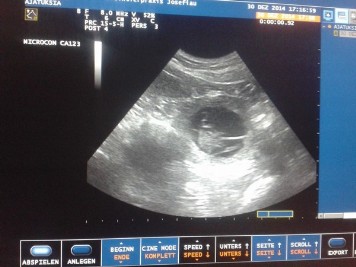

30.01.2014/ Day 25

The ultrasonic showed us at least 5 little puppies with beating heartbeats!